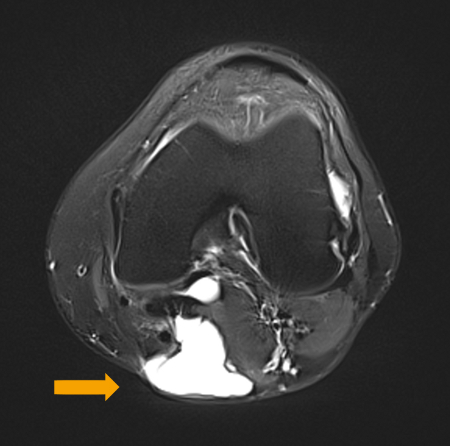

The posterior horn of the medial meniscus is the only reinforcing structure at this location. Degeneration of the medial meniscus, together with conditions where intra-articular pressure increases, makes the weak capsule protrude, giving rise to a popliteal cyst in the posteromedial popliteal fossa.[1][Figure caption and citation for the preceding image starts]: Preoperative T2-weighted MRI showing posterior fluid collection communicating with posterior medial joint in a patient with a popliteal cyst secondary to pigmented villonodular synovitisAdapted from Tosti R, Kelly JD 4th. Pigmented villonodular synovitis presenting as a Baker cyst. Am J Orthop (Belle Mead NJ). 2011;40:528-531; used with permission [Citation ends].